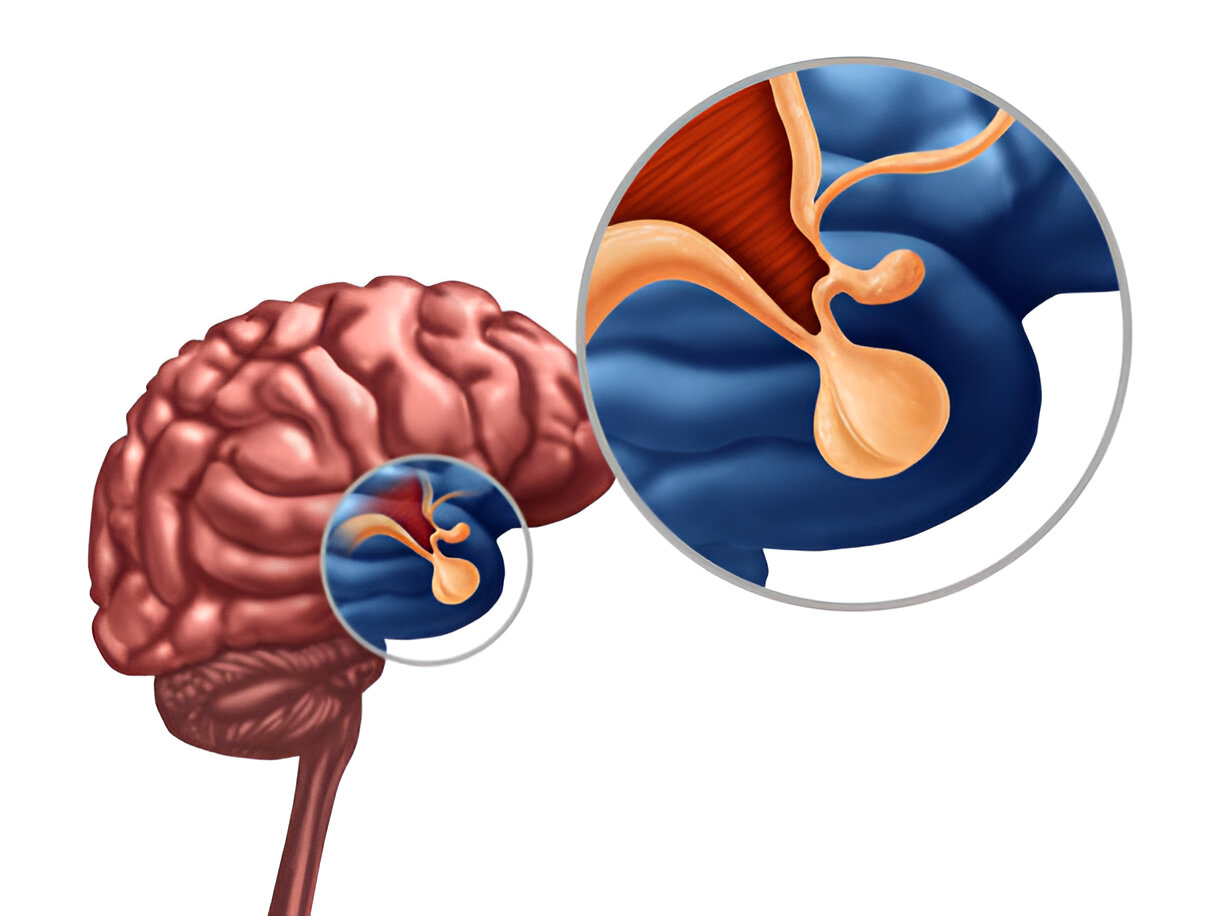

Humans are a powerful network of organs and glands who support each other for a normal functioning of our body. The pituitary gland is a pea-sized gland located at the base of the brain. It is referred to as the master gland as it plays a very crucial role for hormone production.

Pituitary gland is often known as the Master gland as it plays an essential role in regulating the bodily functions. It is situated at the base of the brain, it is a pea-sized powerhouse which is responsible for the growth, metabolism and even reproduction.

The pituitary gland is a pea-sized organ located at the base of the brain. It serves as the central hub for regulating a wide range of vital bodily functions. The gland produces hormones that control growth, metabolism, stress response, and reproduction.